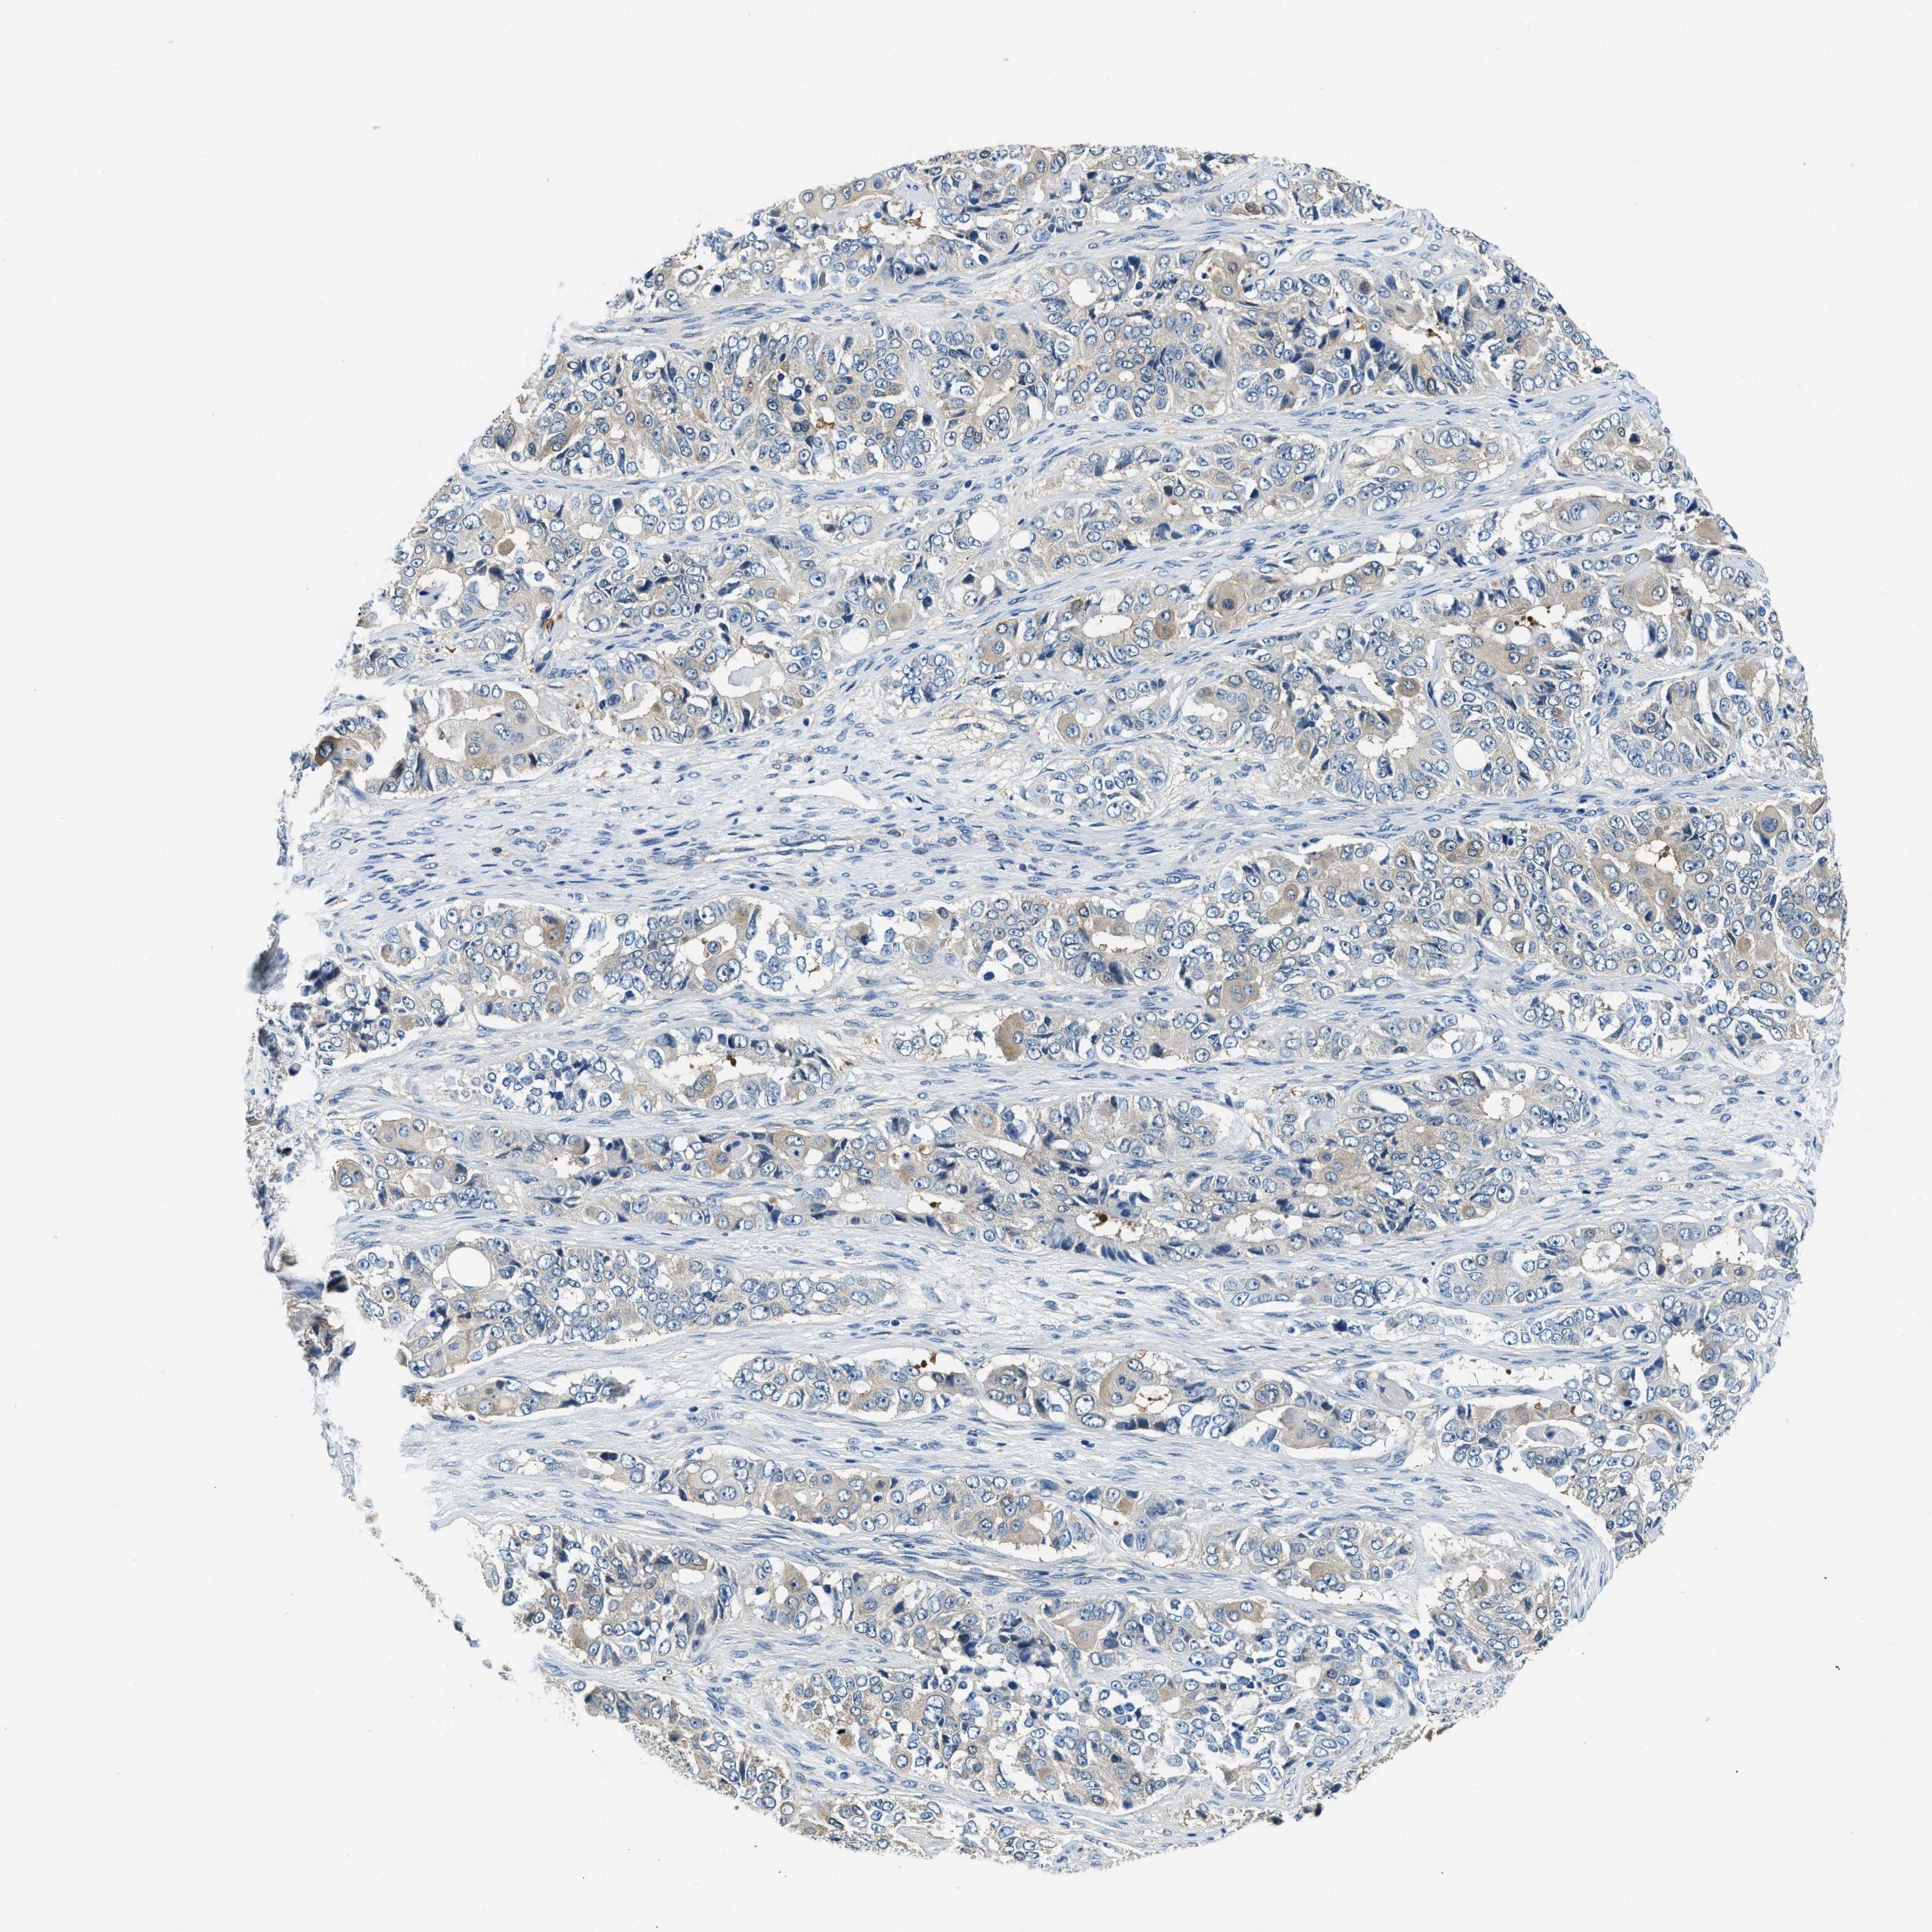

OVARIAN CANCER - Protein expressioni

A mouse-over function shows sample information and annotation data. Click on an image to view it in a full screen mode. Samples can be filtered based on level of antibody staining by selecting one or several of the following categories: high, medium, low and not detected. The assay and annotation is described here.

Note that samples used for immunohistochemistry by the Human Protein Atlas do not correspond to samples in the TCGA dataset.

Antibody stainingi

Antibody staining in the annotated cell types in the current human tissue is reported as not detected, low, medium, or high, based on conventional immunohistochemistry profiling in selected tissues. This score is based on the combination of the staining intensity and fraction of stained cells.

Each image is clickable and will lead to virtual microscopy that enables deeper exploration of all samples and also displays staining intensity scores, fraction scores and subcellular localization as well as patient and tissue information for each sample.

Antibody HPA018116

Staining

High

Medium

Low

Not detected

Intensity

Strong

Moderate

Weak

Negative

Quantity

>75%

75%-25%

<25%

None

Location

Nuclear

Cytoplasmic/membranous

Cytoplasmic/membranous,nuclear

Cystadenocarcinoma, serous, NOS

Carcinoma, endometroid

Cystadenocarcinoma, mucinous, NOS

Carcinoma, NOS